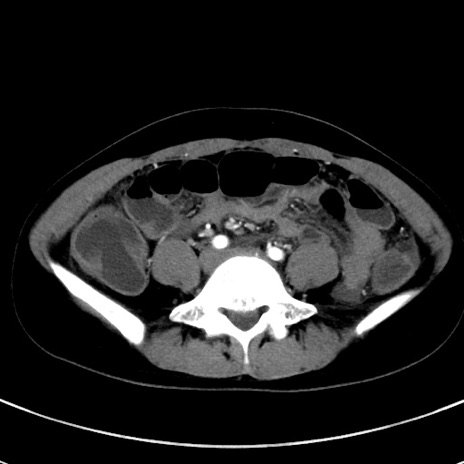

症例17(横断像)

【症例】20歳代女性

【主訴】嘔吐、下腹部痛

【現病歴】昨日夕食後に嘔吐し下腹部痛が出現。本日になっても嘔吐持続し改善しないため来院。

【身体所見】意識清明、BT 37.2℃、BP 108/67mmHg、腹部:平坦、やや硬、下腹部正中から右にかけて圧痛あり、反跳痛軽度あり、tapping pain(+)。

【データ】WBC 13600、CRP 14.94